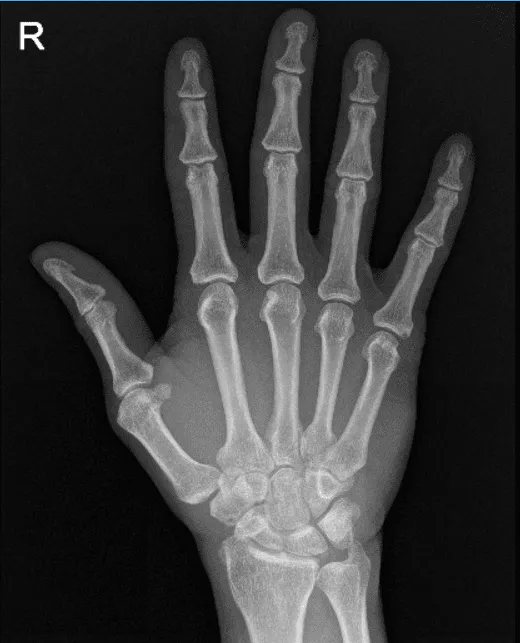

Presentó una radiografía de sus rodillas bilaterales, columna lumbar y mano derecha de Zwanger. Los resultados de sus radiografías mostraron cambios degenerativos osteoartríticos leves. No hay fracturas. Para su columna lumbar, cambios degenerativos lumbares multinivel leves. Para su mano derecha, mano derecha normal.

Rayos X a la derecha 3 o más vistas completas